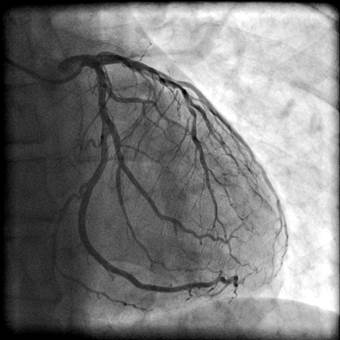

- ангіографія коронарних артерій (мал. 2)

Мал.2. Ангіографія коронарних артерій

Ангіографія коронарних артерій і КТ-коронарографія є методи з контрастуванням судин міокарда, що дозволяє визначити їх прохідність, збереження просвіту, ступінь оклюзії;